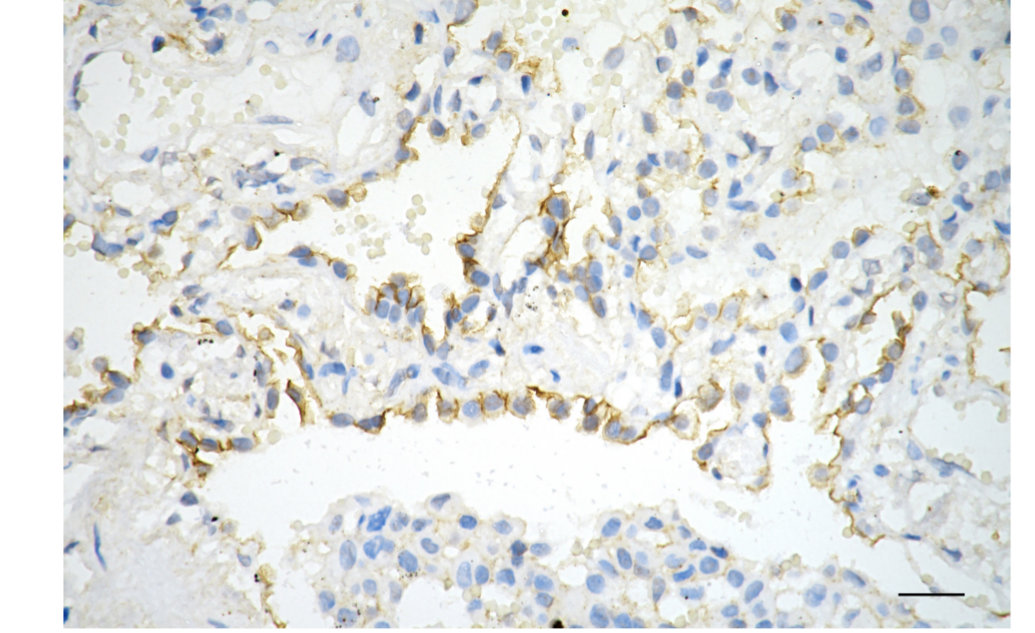

Immunohistochemistry was performed on paraffin-embedded human lung adenocarcinoma using phospho-EGFR (Y1068) antibody. Antigen retrieval was done in sodium citrate buffer (pH 6.0). DAB was used for detection, with hematoxylin counterstaining. Images were acquired using a Nikon Ci-L Plus microscope (40× objective). Scale bar: 25 μm.